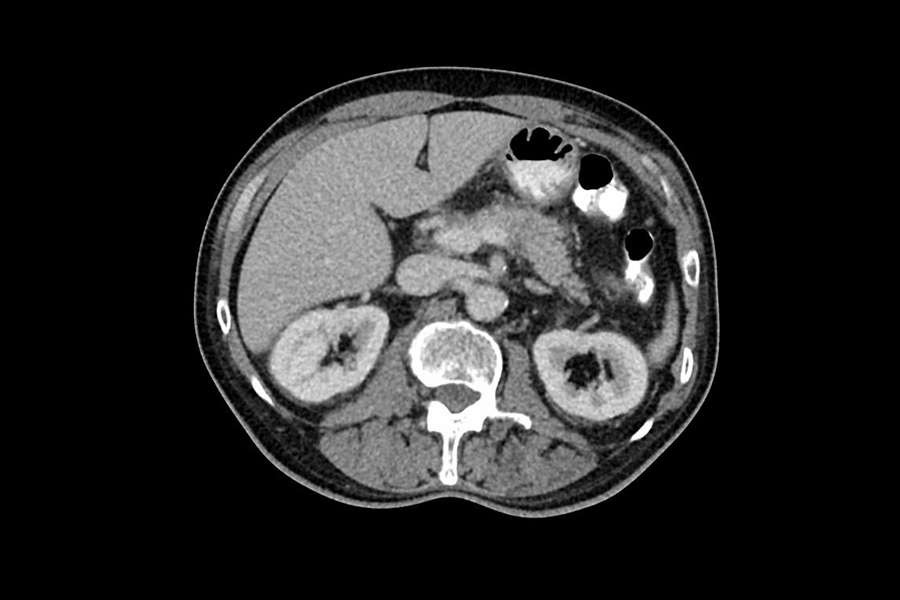

Die CT kann bei allen Körperpartien, einschließlich Herz, Lunge und Bauchraum, zum Einsatz kommen. Auch Skelettverletzungen werdem vom CT sehr gut sichtbar dargestellt, da selbst sehr dünne Knochen deutlich zu erkennen sind.

- Darstellung des gesamten Bauchraumes, einschließlich des Beckens